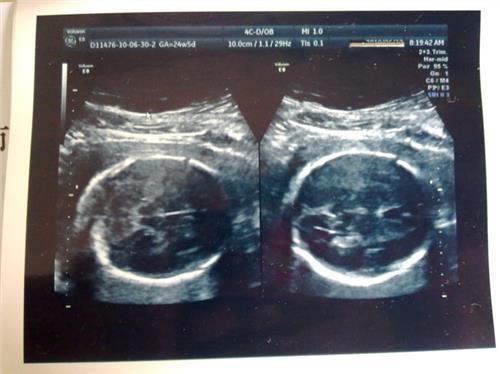

胎儿的双顶径起胎儿生长发育中的一个指标,不同的发育时期,宝宝的双顶径的数值会有所不同,而且每个宝宝也会有小的差异性。一些胎儿双顶径大是什么原因呢?...

胎儿双顶径,这个医用术语生过宝宝的妈妈都不陌生,通常在做B超的时候,医生会通过B超来检测出胎儿双顶径的尺寸,以此来判断胎儿宝宝的发育情况...

男孩双顶径一般是多少?民间一直有双顶径辨男女的说法,那么,双顶径一般多少是男孩呢?在孕24周开始,双顶径减股骨长=1.7以上。此后每次B超双顶径-股骨长就开始逐渐增加。...